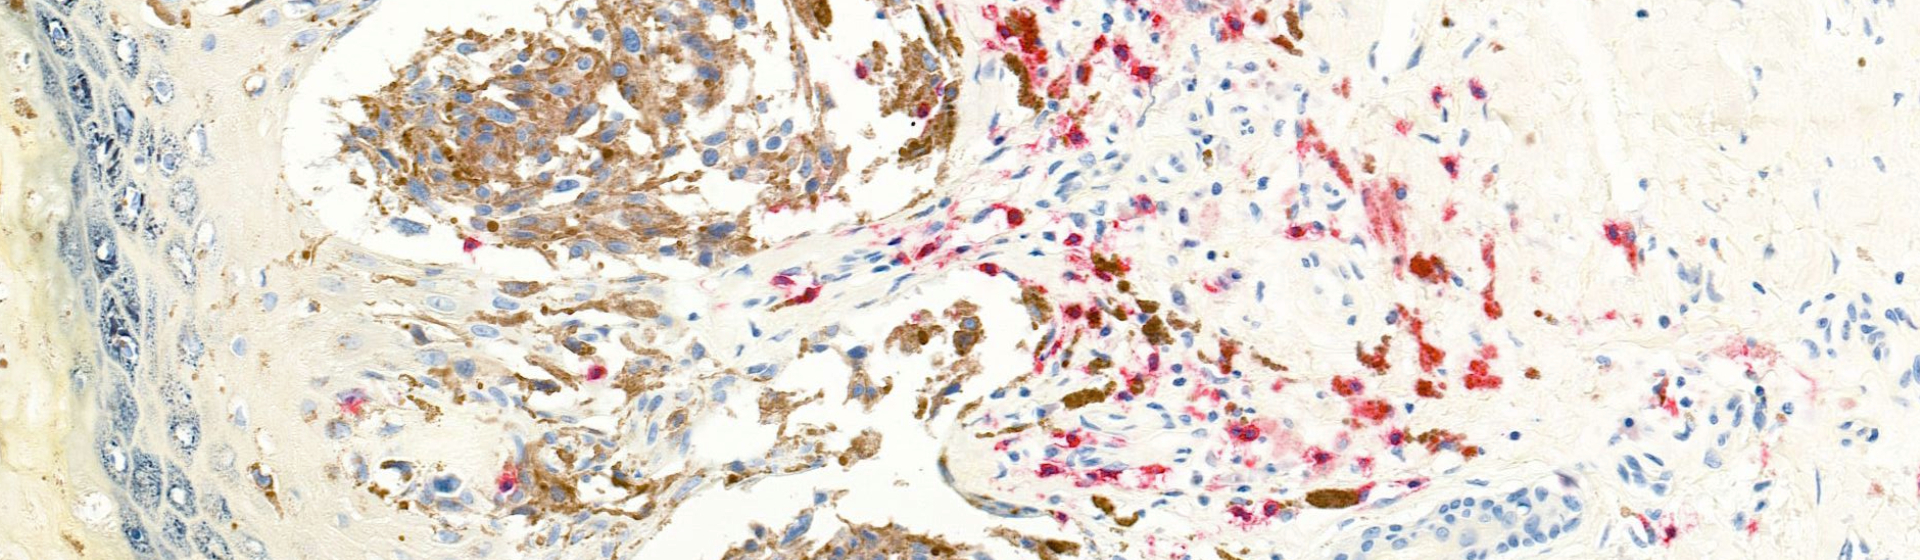

Plasmodium parasites export proteins to the surface of red blood cells, allowing infected red blood cells to stick to the wall of blood vessels. In human malaria, the best characterised of these proteins are encoded by a highly variable family of genes, allowing the parasites to evade the host immune response and continue the infection. Surprisingly basic rules about this gene family are preserved between chimpanzee and human malaria: despite huge variation in the individual sequence of these surface antigen genes, their absolute numbers and the numbers of sub-types are remarkably preserved. By contrast, other surface antigen repertoires differed very significantly in their numbers.